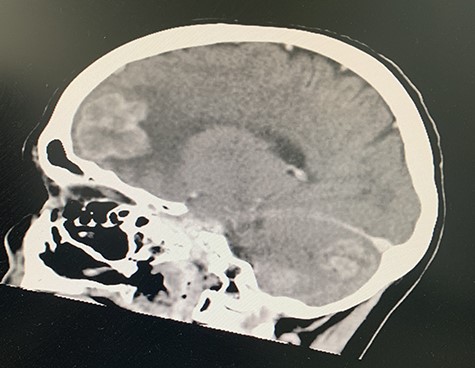

She was referred for urgent respiratory review and discussed at the respiratory Multidisciplinary team (MDT) meeting at a regional referral centre, where staging CT brain revealed six cerebral metastases with two large regions of vasogenic oedema. The metastases were bilateral, but more marked on the right, with the largest lesion in the anteroinferior right frontal lobe producing mass effect on the right lateral ventricle frontal horn and midline shift to the left of 5 mm (Figs 5 and 6). Staging bone scan revealed no bony metastases.